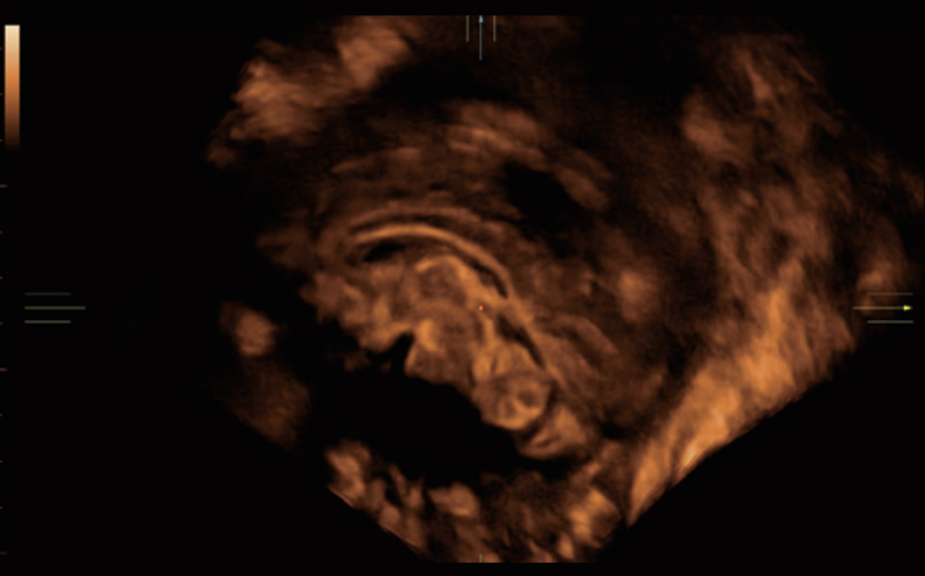

Le Nuewa?I9, con?u spÃĐcialement pour la santÃĐ de la femme et les soins nÃĐonataux, offre une expÃĐrience entiÃĻrement nouvelle gr?ce aux innovations dont il est dotÃĐ, tant à lâintÃĐrieur quâà lâextÃĐrieur. Ces innovations sont dÃĐveloppÃĐes sur la base d'une comprÃĐhension approfondie de scÃĐnarios cliniques complexes, fournissant des rÃĐponses prÃĐcises et adaptÃĐes ainsi qu'une efficacitÃĐ exceptionnelle et une expÃĐrience utilisateur remarquable.

Solution complÃĻte gr?ce au ZST +

La plate-forme ZST+?est une innovation extraordinaire, reprÃĐsentant une ÃĐvolution de lâimagerie ultrasonore. Elle transforme la formation conventionnelle de faisceaux en un traitement basÃĐ sur les canaux de donnÃĐes. Elle repousse les limites de lâimagerie conventionnelle et du compromis entre rÃĐsolution spatiale, rÃĐsolution temporelle et uniformitÃĐ tissulaire en offrant une qualitÃĐ dâimage exceptionnelle pour des solutions dâimagerie infinies et en constante ÃĐvolution.